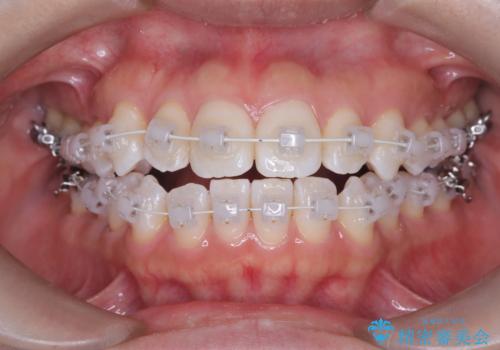

治療は、白いコーティングが施されたワイヤーを使用した審美性の高い装置にて行っています。

本症例では、治療の途中で**バイトアップ(咬み合わせを一時的に挙上する処置)**を行い、

上下の歯が干渉しない環境を作りながら、捻転や叢生の改善を進めました。

これにより、歯を無理に動かすことなく、効率的かつ安全に歯列を整えることが可能となります。

装置には、ワイヤーに白いコーティングが施された審美性の高いワイヤー矯正装置を使用し、

治療中も目立ちにくい配慮を行いました。